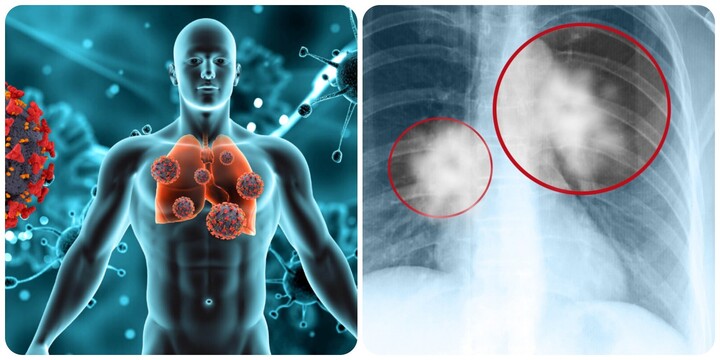

8 dấu hiệu cảnh báo ung thư phổi không nên bỏ qua

Ung thư phổi là một trong những căn bệnh ung thư nguy hiểm, nhận biết sớm dấu hiệu cảnh báo bệnh sẽ giúp cho việc điều trị thuận lợi hơn.

Ung thư phổi là một trong những căn bệnh nguy hiểm do khối u ác tính gây ra, nếu không được phát hiện và điều trị kịp thời sẽ gây ra những biến chứng nguy hiểm, thậm chí là tử vong.